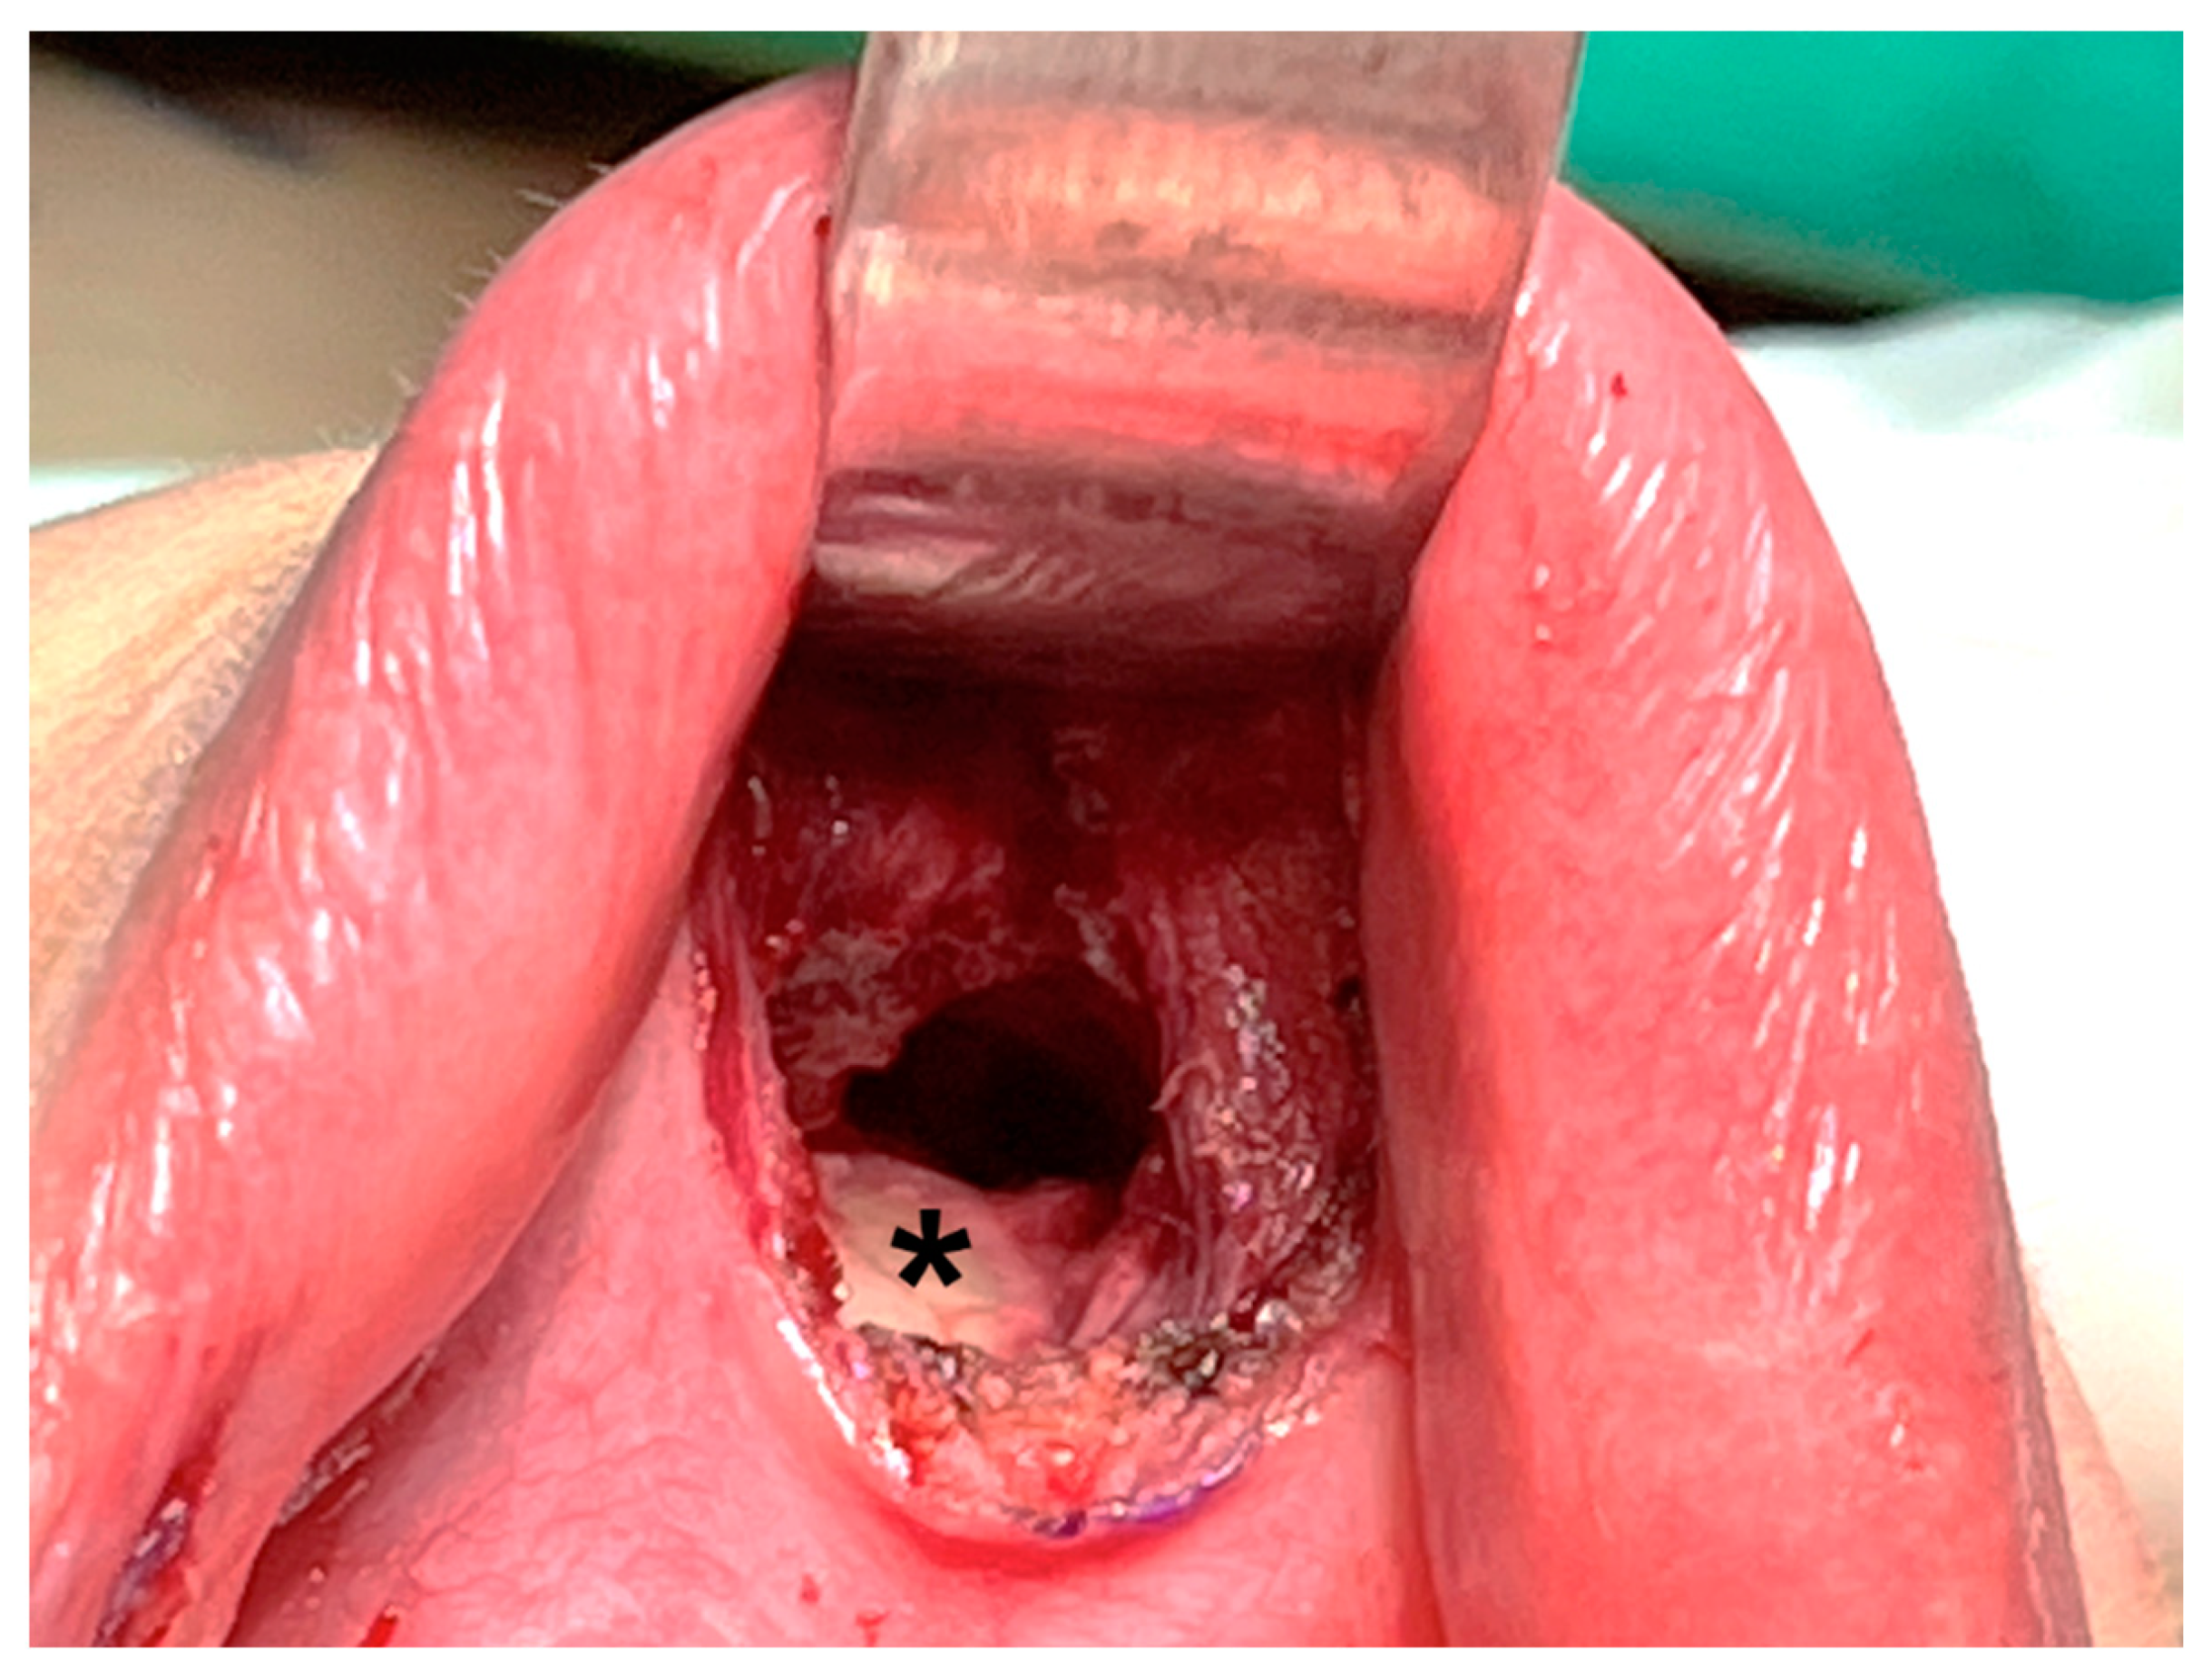

After incising the oral mucosa, the central incision was further dissected down to the lower edge of the mandible with an electrocautery or Kelly clamp. The mentalis muscle might be cut or penetrated during this process [18,35,36,37,38]. This injury might lead to uncoordinated movement of the lower face during pronunciation or smiling [39,40]. In addition, skin perforation might occur due to heat transmission from electrocautery [41] or direct penetration by applying excessive force using a Kelly clamp (Figure 3). Initial occult injury in such a thin flap might also lead to skin dimpling that does not resolve over time and affects the patient’s aesthetic outcome [42]. Great care should be taken to check the thickness of the chin flap at this stage.

Figure 3.

Chin perforation (arrow) by inadvertent use of Kelly clamp during central tract dissection.